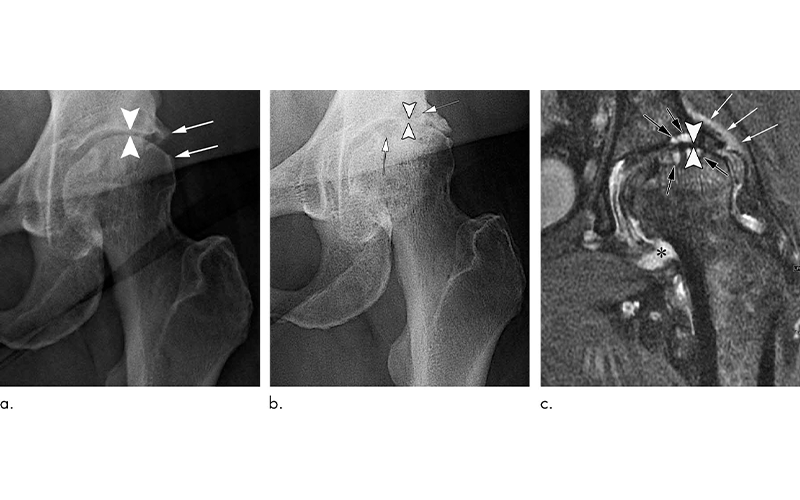

In a review of existing literature on complications after treatment with corticosteroid injections, Dr. Guermazi and colleagues identified four main adverse findings: accelerated osteoarthritis progression with loss of the joint space, subchondral insufficiency fractures (stress fractures that occur beneath the cartilage), complications from osteonecrosis (death of bone tissue), and rapid joint destruction including bone loss.

The researchers recommend careful scrutiny of patients with mild or no osteoarthritis on X-rays who are referred for injections to treat joint pain, especially when the pain is disproportionate to the imaging findings. Prior research has shown that these patients are at risk of developing rapid progressive joint space loss or destructive osteoarthritis after injections.

Physicians may also want to reconsider a planned injection when the patient has acute change in pain not explained by X-rays as some underlying condition affecting joint health may be ongoing, the researchers said. Most importantly, younger patients and patients earlier in the course of the disease need to be told of the potential consequences of a corticosteroid injection before they receive it.

“Physicians do not commonly tell patients about the possibility of joint collapse or subchondral insufficiency fractures that may lead to earlier total hip or knee replacement,” Dr. Guermazi said. “This information should be part of the consent when you inject patients with intra-articular corticosteroids.”